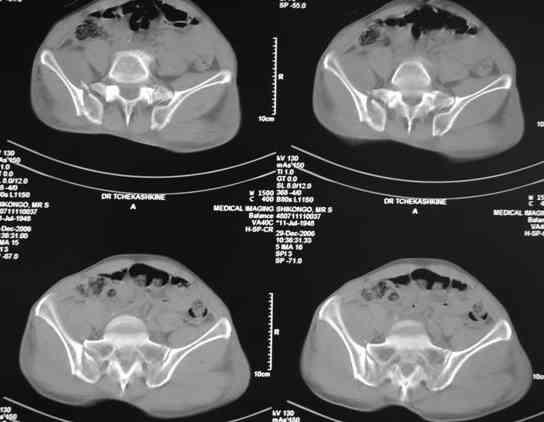

По-поводу фиксации таза спонгиозными винтами. Данный способ все-таки показан для фиксации повреждения крестцово-подвздошного сочленения или переломов крестца. Мне кажется, что в данной случае ситуация иная - имеется перелом "основания" крыла подвздошной кости (в который вовлечена и поверхность, составляющая крестцово-подвздошное сочленение). Не уверен, что фиксация данного повреждения (и заднего полукольца) винтами будет стабильной, так как именно на уровне 1-2 крестцовых позвонков (где обычно вводят винты) линия перелома уходит в латеральном направлении от крестцово-подвздошного сочленения.

По-поводу репозиции костей таза. Производить репозицию костей все-таки необходимо. Пока я не встретил информации, сколько времени прошло с момента травмы, но одномоментно низвести правую половину таза может быть тяжело, учитывая и наличие перелома бедренной кости (что затруднит тракцию за нижние конечности).

Я просмотрел томограммы и у меня создалось впечатление, что винтам есть за что *зацепиться*. В сочетании с 5 мм Шанц винтами, проведенными через нижне-переднюю ость спереди назад через КП сочленения -стабильность тазового кольца должна восстановиться. - Это , конечно, при условии , что закрытая рнепозиция будет успешной.

PI>По-поводу репозиции костей таза. Производить репозицию костей все-таки необходимо. Пока я не встретил информации, сколько времени прошло с момента травмы, но одномоментно низвести правую половину таза может быть тяжело, учитывая и наличие перелома бедренной кости (что затруднит тракцию за нижние конечности).

Травма произошла 22 или 23 декабря, ко мне больной попал 26 декабря, 3 января -остеосинтез перелома бедра и внутр.лодыжки.

после КТ отказался от этой идеи - двусторонний перелом крестца в зоне 1 - алярная часть, при попытке низведения правого гемипелвиса теоретически есть вероятность смещения

фрагмента крестца слева.